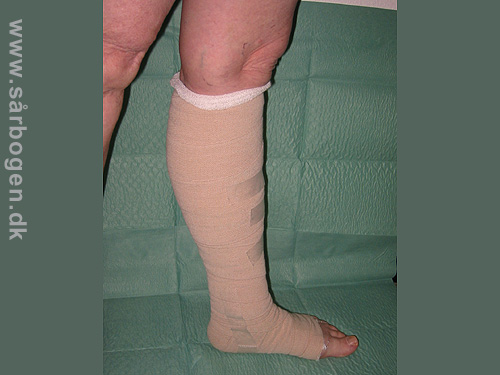

Kompressionbandage

Zoom